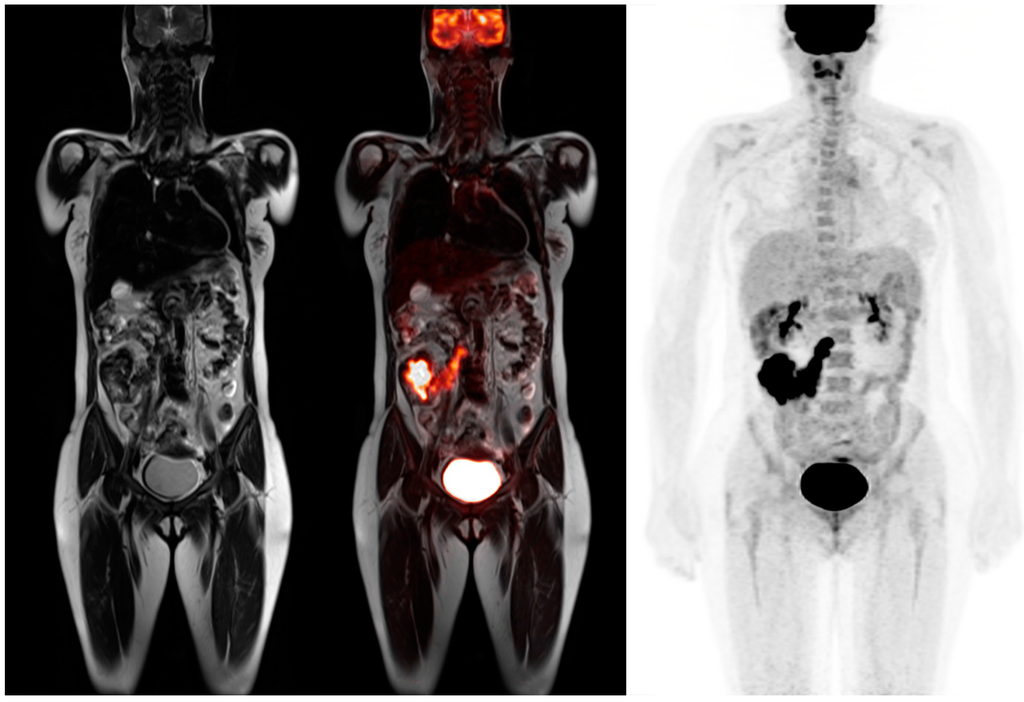

Pancreatic cancer is diagnosed using multiple modalities including abdominal ultrasound, endoscopic ultrasound, endoscopic retrograde cholangiopancreatography, CT, MRI, and PET/CT. For staging purposes, current recommendations include cross-sectional imaging such as contrast enhanced CT or MRI. PET-CT imaging has played an important role in characterizing pancreatic lesions and its metastatic spread. Most malignant tumors of the pancreas are active on FDG PET imaging and PET-CT has much higher sensitivity and specificity than contrast enhanced CT [35] as illustrated in Figure 5. MRI is frequently employed to evaluate pancreatic lesions because of its superior soft tissue contrast resolution. MRI can additionally evaluate for pancreatic duct dilatation and collateral vein dilatation in addition to assessing necrosis, cystic changes, and fibrosis [36].

Figure 5.

62-year-old male for initial staging of pancreatic adenocarcinoma. The PET-MRI axial fusion image shows a large hypermetabolic mass in the body of the pancreas (top left). The T1 axial image demonstrates a mass in the pancreatic body that is isointense to the normal pancreatic tissue (top right). The T2 axial images show considerable main pancreatic duct dilatation (bottom left). The PET axial image displays intense metabolic activity within the pancreatic tumor relative to the liver activity with standardized uptake value of 8.7.

Nagamachi et al. examined 119 patients with pancreatic lesions and compared PET-MRI to PET-CT images. PET-MRI demonstrated higher accuracy of 96% vs. 86% in the assessment of pancreatic tumors in comparison to PET-CT [37]. PET-MRI offers better lesion detection, characterization, and definition. Even non-contrast enhanced PET-MRI body sequences offered superior image quality compared to PET-CT [38]. FDG PET-MRI could accurately detect encasement of vessels, infiltration of surrounding structures, and invasion of the common bile duct that are not well delineated on PET-CT [37]. It seems like both PET-CT and PET-MRI are cost effective by determining patient who undergoes futile laparotomy by detecting distant metastases [39].